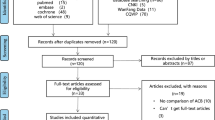

A total of 130 people were approached to participate, and 100 patients were included in the study. Among them, 5 patients withdrew informed consent, and 4 patients failed to complete the follow-up. The remaining 91 patients in the study completed the trial (Fig. 1). There was no significant difference in age, body mass index, height, weight, operation time, tourniquet time, or intraoperative bleeding between the ropivacaine group and the saline group (Table 1).